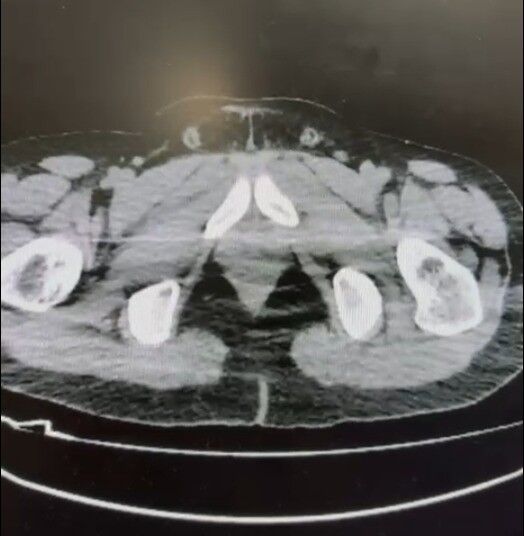

Şüphelilerin uyuşturucu maddeleri "yutma yöntemi" ile mide ve bağırsaklarında taşıdığı belirlendi. Düzenlenen baskın sonrası yapılan aramalarda, 101 kapsül halinde paketlenmiş tam 722 gram uyuşturucu madde ele geçirildi. Sadece uyuşturucu değil, bu yöntemi uygulamak için kullanılan çeşitli materyaller de polisin dikkatinden kaçmadı. Ayrıca zanlıların üzerinde ve adreslerinde uyuşturucu ticaretinden elde edildiği anlaşılan 20 bin 210 TL, bin 320 euro ve 10 ABD doları ile hassas teraziye el konuldu.